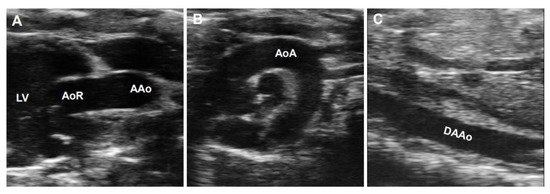

Doppler ultrasonography employs the Doppler effect to generate imaging of the movement of tissues or body fluids (usually blood) and their relative velocity to the probe. By calculating the frequency shift of a particular sample volume, its speed and direction can be determined and visualized. There are several applications with Doppler ultrasonography, such as CD, SD, and tissue Doppler images (TDI). While CD ultrasonography provides an image showing blood flow by the bright areas of aliasing (Figure 5A–C) and turbulence in the aorta’s narrowed segment, SD imaging provides quantitative data on blood velocities, enabling flow volumes and pressure gradients to be calculated (Figure 5D–F). An important characteristic of the waveform is the peak systolic velocity, which increases as the luminal diameter decreases, such as in the setting of stenosis. Vessel tortuosity and branching can lead to either focally increased or decreased velocity, resulting in a flow disturbance or even flow reversal [50]. These characters of Doppler images are similar in humans (Figure 5A–F) and rodents (Figure 6A–D).

Figure 5. Representative Doppler signals and velocity waveforms of a human aorta. Images were obtained from a 20-year-old male volunteer representing Doppler images of the apical five-chamber view (A) and three-chamber view (B) of the aortic root (AoR) and the suprasternal view of the aortic arch (AoA) (C). (DF): The corresponding assay of the aortic velocity of (AC). LV: left ventricle, LA: left atrium, RV: right ventricle, RA: right atrium.

Diagnostics 11 00454 g005

Figure 6. Color Doppler(CD) and pulsed-wave images from a mouse aorta. The representative images by CD were obtained from a healthy four-month-old C57BL/6J mouse. (A,B): CD images of the aorta arch (AoA) (A) and descending abdominal aorta (DAAo) (B). (C,D): The corresponding Inflow velocity of (A,B) using pulsed-wave Doppler imaging.

Diagnostics 11 00454 g006